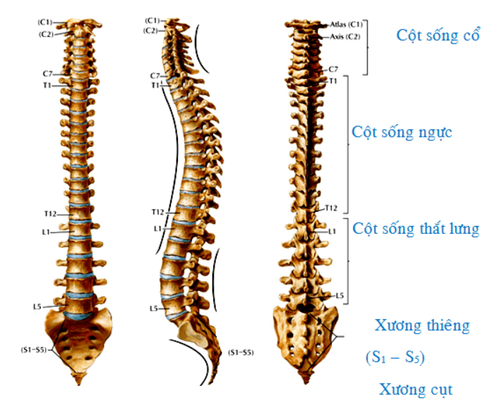

Chụp cộng hưởng từ thắt lưng là một trong những kỹ thuật chẩn đoán về hình ảnh hiện đại nhất, có thể giúp nhìn thấy được những hình ảnh tổn thương cột sống của người bệnh một cách chi tiết. Để thực hiện kỹ thuật này, cơ thể bệnh nhân sẽ được đi vào vùng từ trường mạnh, nhằm đồng hóa được chiều chuyển động của các nguyên tử Hydro trong những phân tử nước thuộc cơ thể con người.

Việc chẩn đoán và đánh giá những bệnh lý liên quan đến cột sống thắt lưng sẽ trở nên dễ dàng và chính xác hơn nhiều nhờ vào những hình ảnh thu được từ kỹ thuật chụp cộng hưởng từ thắt lưng. Kỹ thuật này sẽ hỗ trợ cho thấy cấu trúc, hình thái, và những tổn thương dây chằng, phần mềm, mô mềm, đĩa đệm một cách chân thực và rõ nét nhất.

Hình ảnh thu được từ chụp cộng hưởng từ có độ phân giải cao, chi tiết giải phẫu tốt, giúp nâng cao chất lượng chẩn đoán. Thông thường, chụp MRI sẽ được các bác sĩ khuyến khích bệnh nhân thực hiện khi người bệnh bị đau lưng trong thời gian dài những hình ảnh thu được từ chụp X-quang không rõ, khó xác định. Ngoài ra chụp cộng hưởng từ thắt lưng còn mang đến nhiều thông tin hữu ích cho việc chẩn đoán một số tổn thương ở tủy sống, đốt sống, đĩa đệm... như:

- Chấn đoán các bệnh lý ở cột sống và thắt lưng, đánh giá rễ thần kinh, chèn ép tủy sống...